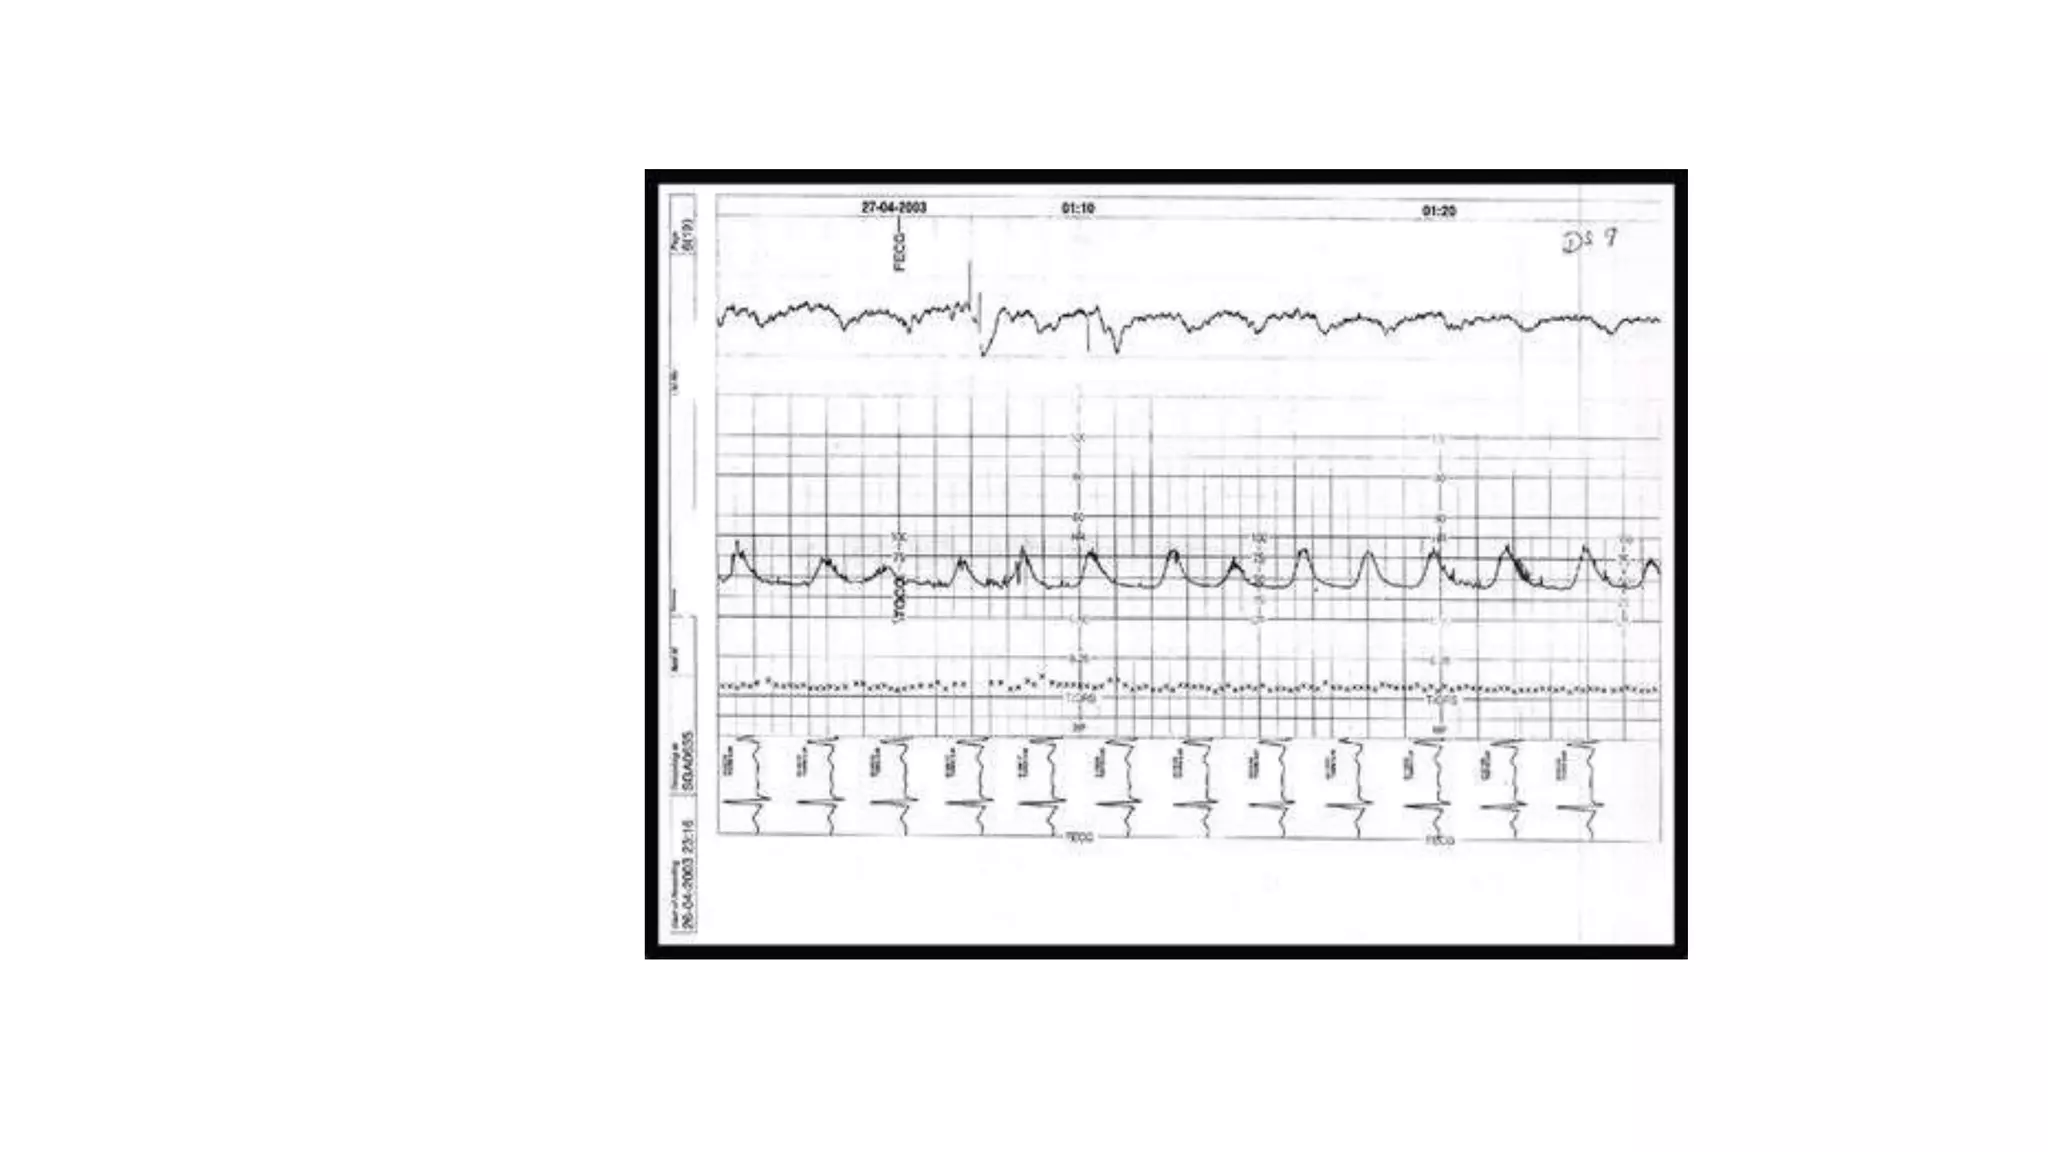

The document discusses key metrics for monitoring a baby's heart rate in utero, including the normal baseline rate of 100-160 bpm and variability. It also covers types of accelerations and decelerations that can occur, such as early or late, as well as bradycardia, which is an abnormally slow heart rate.